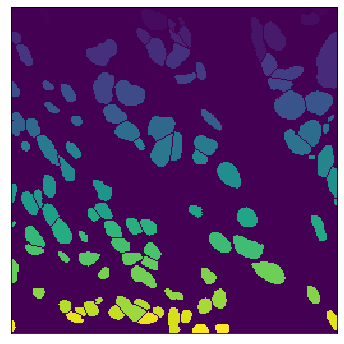

The field of computational pathology has witnessed great advancements since deep neural networks have been widely applied. These deep neural networks usually require large numbers of annotated data to train vast parameters. However, it takes significant effort to annotate a large histopathology dataset. We propose to build a data-efficient model, which only requires partial annotation, specifically on isolated nucleus, rather than on the whole slide image. It exploits shallow features as its backbone and is light-weight, therefore a small number of data is sufficient for training. What's more, it is a generative compositional model, which enjoys interpretability in its prediction. The proposed method could be an alternative solution for the data-hungry problem of deep learning methods.